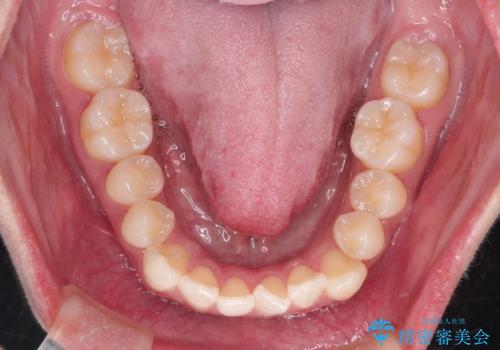

- 口元をさげたいという主訴で来院されました。4番の歯を4本抜歯し、遠心移動とIPRをしました。右上2番が矮小歯のため見た目を重視するならクラウンの提案をしましたが、そのままでの治療を希望されました。

矯正治療の最終段階でスペースクローズにやや時間がかかりましたが、前歯が下がったことで口元の位置も下がりきれいになりました。